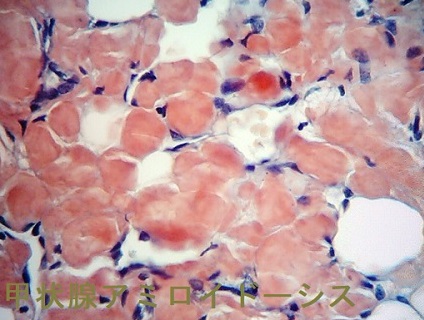

橋本病に合併した結節性甲状腺アミロイドーシスの病理組織標本では、

- アミロイド結節内の甲状腺濾胞構造は破壊され、異物反応や石灰化も存在する(第57回 日本甲状腺学会 P2-061 橋本病に合併した甲状腺amyloidosis の一例)

- アミロイド結節周囲の甲状腺組織には、リンパ球・形質細胞の炎症性細胞浸潤とリンパ濾胞形成を認めます。これらのリンパ球・形質細胞が、IgGのκ鎖を産生するのが原因では?と推察しますが、原因不明です。(第58回 日本甲状腺学会 P1-12-3 橋本病に合併した甲状腺限局免疫グロブリン軽鎖amyloidosisの一例)

- アミロイド沈着物は、細胞質内に小アミロイド滴を含む多数の組織球と多核巨細胞に囲まれる。しかし、血管壁にアミロイド沈着は無し。免疫組織化学検査により、アミロイドはアミロイドP成分、IgG、κ軽鎖が強陽性で、IgG、特にκ軽鎖(AL)が前駆体タンパク質と判明。[Acta Pathol Jpn. 1992 Mar;42(3):210-6.]。

甲状腺アミロイドーシスの細胞診では通常、写真のように無構造好酸性物質を認め、その中に線維芽細胞が増生しています。濾胞組織は破壊され、細胞成分は少ない。

甲状腺アミロイドーシスの組織診